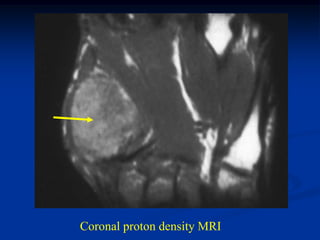

Case #609

30 year male

sessile based

osteochondroma

humerus

Coronal T-1 MRI

Coronal proton density MRI

cap

Axial T-1 MRI

fatty marrow

Axial T-2 MRI